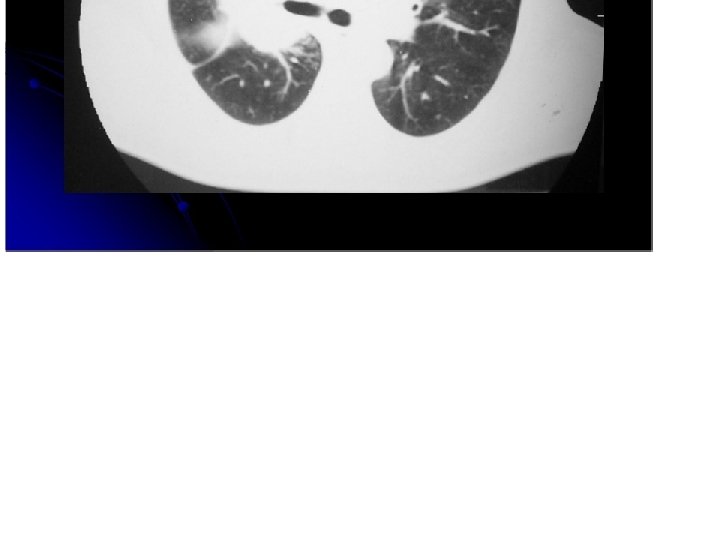

adenocarcinoma

Aden ocarcinoma. • • • se puede presentar como un nódulo una zona de consolidación varios nódulos producen mucha secresión Sospechar en caso de neumonías que no se resuelven.